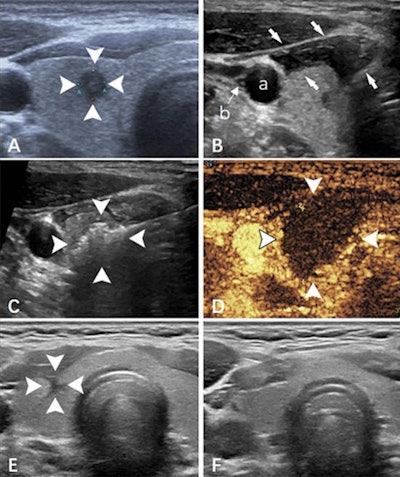

Ultrasound images show papillary thyroid carcinoma in the right lobe of the thyroid in a 36-year-old man. (A) Imaging shows the tumor pre-ablation (arrowheads). (B) The hydrodissection technique (arrows) was used to protect the carotid artery (a) and vagus nerve (b). (C) Imaging shows a hyperechoic pattern in the tumor during the ablation procedure (arrowheads). (D) Postablation contrast-enhanced imaging shows no enhancement in the tumor area (arrowheads). (E) Imaging shows the ablation zone six months after ablation (arrowheads). (F) The ablation area has almost disappeared one year after ablation. Images and caption courtesy of Radiology.Zheng and co-authors sought to compare the feasibility, effectiveness, and safety of microwave ablation for treating these microcarcinomas with and without ultrasound-detected capsular invasion via a study that included data from 460 patients. Of these, 82 underwent microwave ablation with ultrasound-guided detection of capsular invasion while the remaining 378 did not. The capsular invasion group had follow-up at 20 months while the noninvasion group had follow-up at 21 months.

The team found comparable success rates for microwave ablation with ultrasound for both groups, at 99% for the capsular invasion group and 100% for the non-invasion group. It also reported only one complication (1%) in the capsular invasion group compared with 11 in the noninvasion group (3%). On follow-up, the team reported clear shrinkage of the ablation zone in both groups, at 97% in the capsular invasion group and 96% in the noninvasion group.